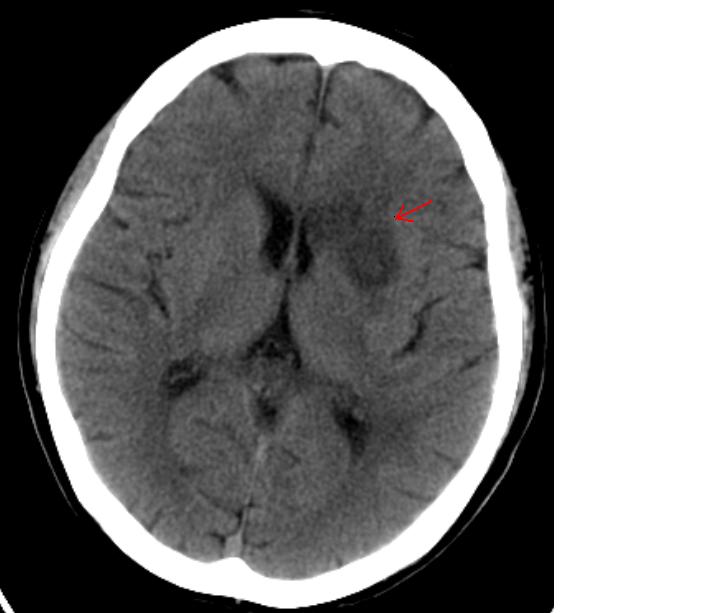

因脑供血血管突发阻塞所引起的卒中称为缺血性卒中。占全部卒中的60-80%

因局部血管破裂导致血液外溢,侵入脑组织所引起的卒中称为出血性卒中